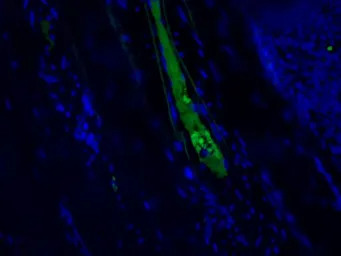

IF staining of human kidney with GTX49368. Strong staining of veins of nephritis kidney. Dilution: 1:200.